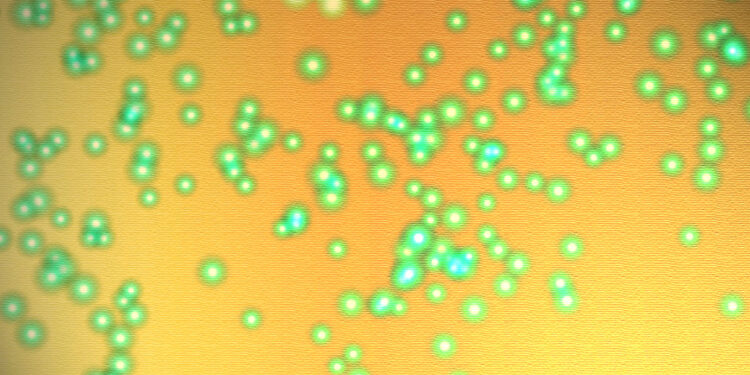

First Inset Image Courtesy of Dr. Yale Rosen Atlas of Pulmonary Pathology Flickr page – Creative Commons License